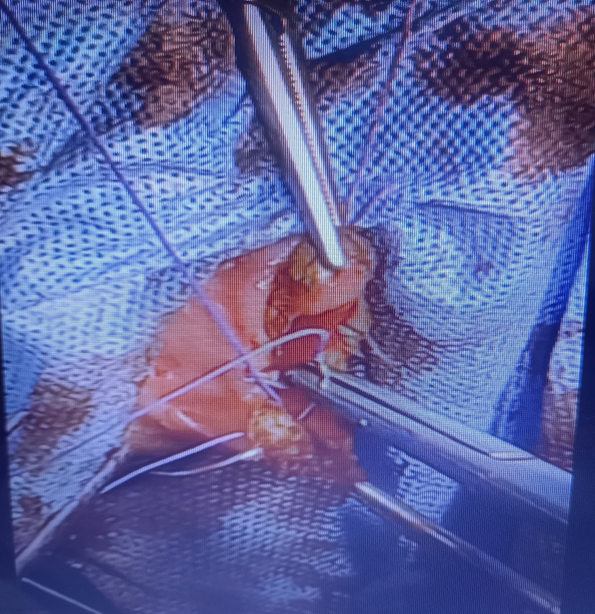

The patient underwent a hymenotomy and surgical drainage of the hematocolpos. A circular (annular) incision at the center of the bulging hymen was performed by electrocautery, followed by drainage of approximately 2500ml of thick brownish menstrual blood and diligent irrigation of the vagina (Figure 4). Care was taken to spare hymenal tissue circumferentially from the base in order to preserve virginity. A normal cervix was visualized and inspected. The vaginal entrance was surgically restored as follows: The edges of the vaginal margins were everted by suturing the inner vaginal mucosa to the exterior vestibular mucosa with absorbable No2 sutures, firstly by performing single interrupted sutures which were then followed by a purse-string suture (Figure 5). Vaginal swabs were collected and the results of the cultures were negative for infection. A penrose tube was placed at the introitus to ensure unimpeded continuous drainage and was removed on the second postoperative day. Broad-spectrum antibiotics were administered for post-operative chemoprophylaxis. The postoperative course was uncomplicated and the patient was discharged on the fourth postoperative day. Her wound had completely healed by the time she had her three-month post-op follow-up appointment (Figure 6). To this day, she has been experiencing normal painless menses.

Figure 5 Placement of sutures at vaginal margins.